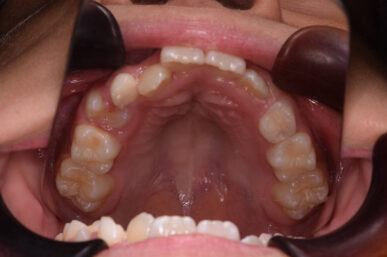

• After

治療の開始が遅く、犬歯と奥歯の生え代わりが始まっていましたが、床矯正より治療スピードが早いアライナー矯正を使用して、犬歯のスペースをとても短期間に作ることができました。八重歯を防げましたので固定式の装置は必要なくなりました。永久歯がすべて生えるまでは予防歯科で歯の生え代わりと機能を管理します。